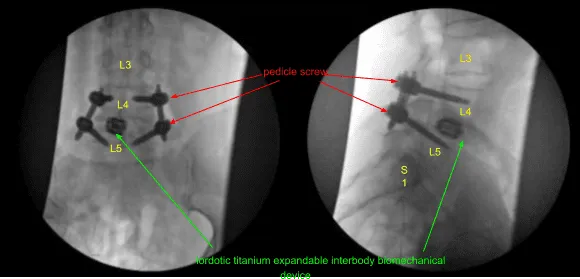

Empezamos por el lado izquierdo. La piel se abrió con un bisturí #15. La hemostasia se obtuvo con Bovie y la fascia se dividió fuertemente con la Bovie. Se colocaron tornillos de pedículo de titanio de 6,0 x 45 mm con neuronavegación en los pedículos L4 y L5 izquierdos usando neuronavigation.

Un dispositivo biomecánico intersomático extensible de titanio lordótico de 22 mm de longitud fue colocado a través de un insertador en el interespacio bajo guiado fluoroscópico AP y lateral, y ampliado hasta el ajuste y la rigidez adecuados. Se retiró el insertador. El separador tubular fue luego retirado mediante visualización microscópica para confirmar la hemostasia con el electrocaute bipolar.

A continuación, se colocaron tornillos pediculares de titanio de 6,0 x 45 mm canulados y auto-roscados sobre los cables K en L4 y L5 del lado derecho bajo guía fluoroscópica. Se quitaron los cables K. Los tornillos avanzaron hasta lograr la sujeción y profundidad adecuadas. Las señales de neuromonitorización se mantuvieron estables en todo momento. El paciente fue vuelto a colocar con el drapeado.

Se realizó una segunda tomografía computarizada intraoperatoria que mostró la correcta posición de todo el hardware e instrumentación implantados. A continuación, se usaron pinzas para determinar la longitud de las varillas de titanio precortadas y predefinidas que se colocaban a lo largo de las cabezas de tulipán bilaterales de instrumentación no segmentaria L4-5 y se aseguraban con tapones de bloqueo.

Estos se tensaron primero en L5 bilateralmente y luego en L4 para lograr la reducción de la espondilolistesis. Se logró una reducción aproximada del 50%. Los tapones de bloqueo se apretaron finalmente con un dispositivo de par y antipar. Luego se retiraron las lengüetas extensoras de los tornillos pediculares. Las heridas fueron irrigadas abundantemente. La hemostasia se confirmó de nuevo.